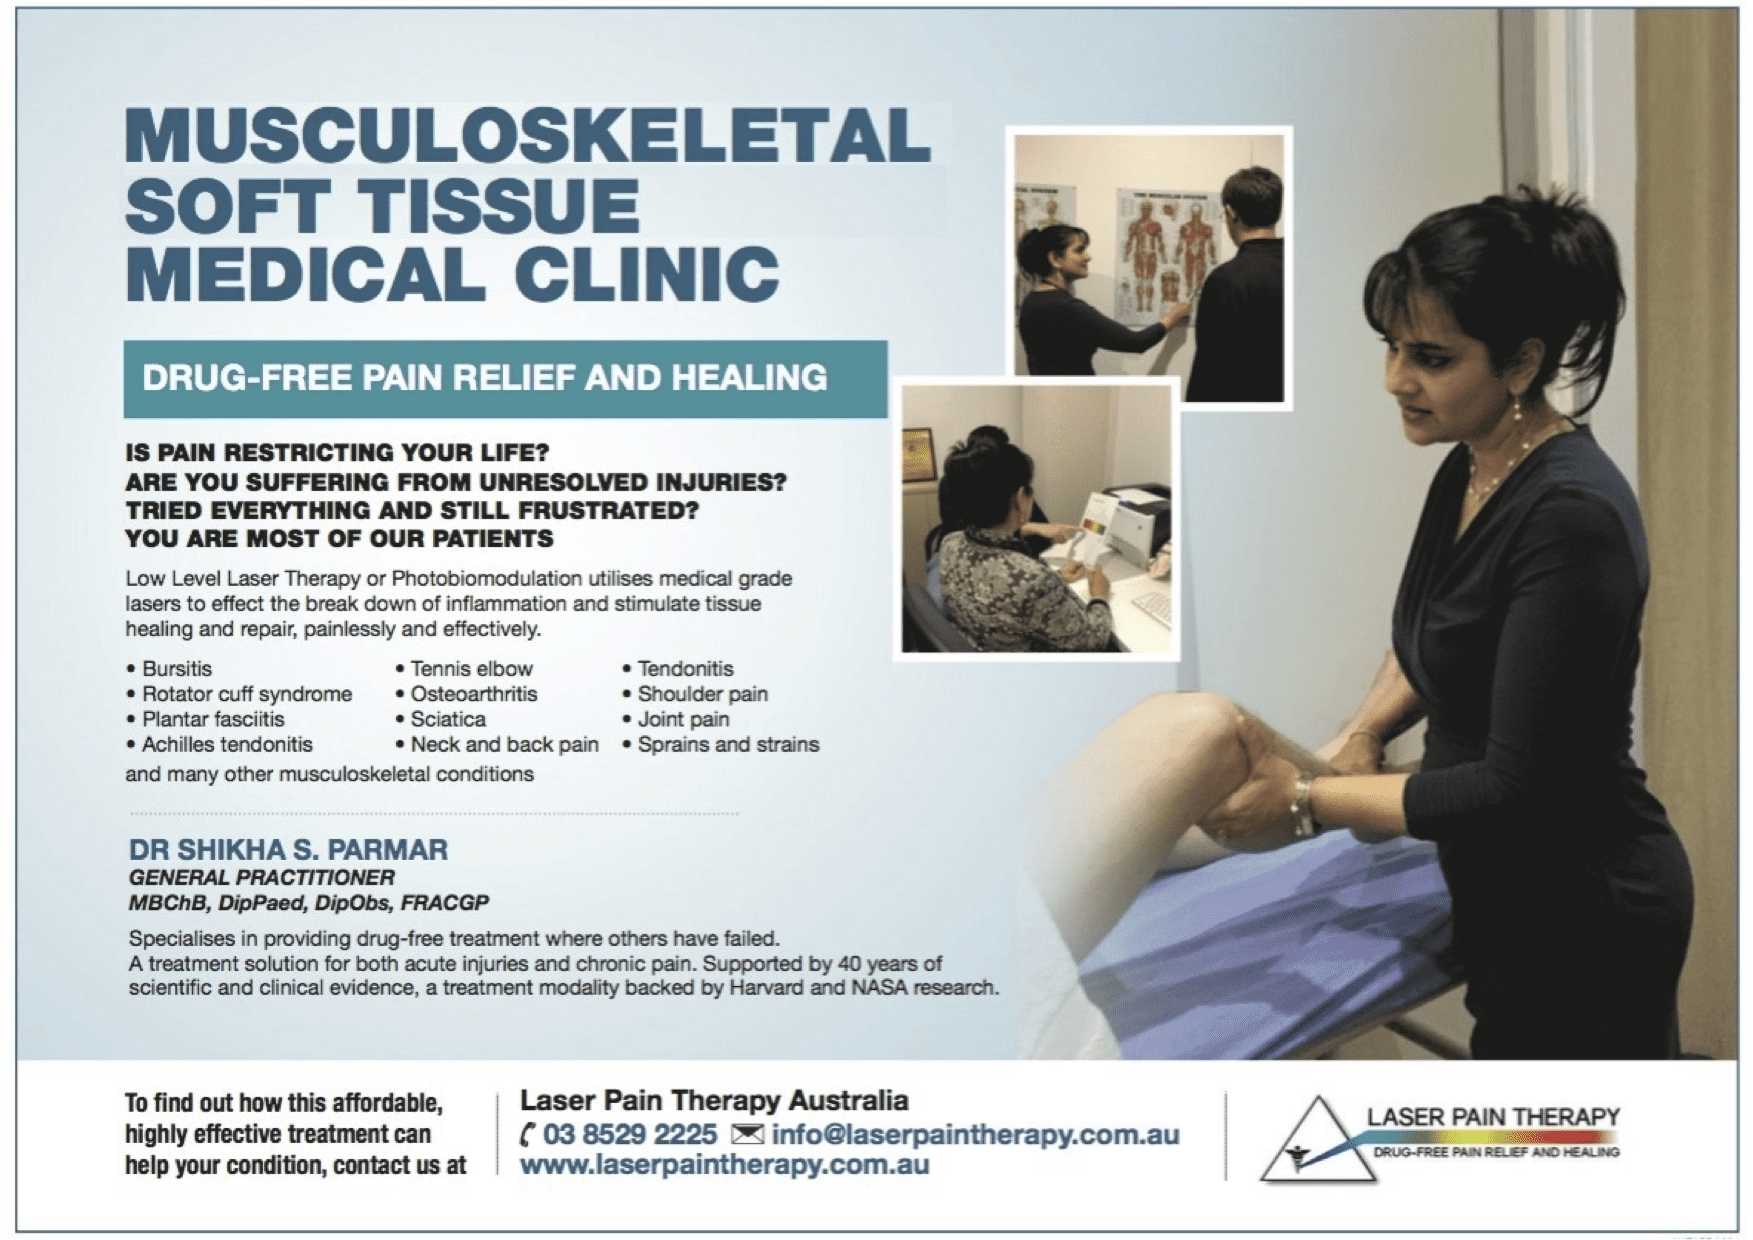

Low-Level Laser Therapy (LLLT), also known as Photobiomodulation Therapy (PBMT), is a highly effective, non-invasive, and drug-free treatment for Sever’s Disease in Melbourne, Victoria. Led by Dr Shikha Parmar, a GP with expertise in managing and resolving chronic musculoskeletal pain, Laser Pain Therapy incorporates LLLT as part of a holistic treatment plan. LLLT is a completely safe, painless treatment modality that targets the underlying cause of the injury rather than simply masking the pain, as pain medications often do. Supported by research from reputable institutions, including Harvard University and NASA, LLLT is an evidence-based therapy for musculoskeletal conditions, including Sever’s Disease.

- At Laser Pain Therapy, all LLLT treatments are GP-led by Dr Shikha Parmar, with a structured treatment program tailored to each patient’s needs.

All patients are assessed by Dr Shikha Parmar (GP). Treatment is delivered within a structured six-week program, including:

- Up to 12 LLLT sessions

- Review after 6 sessions

- Individualised advice and activity modification

- Guided rehabilitation for durable recovery

Patients who respond typically show 15–20% improvement within the first 6 sessions, with best-case improvement of 70–90% over the full program.